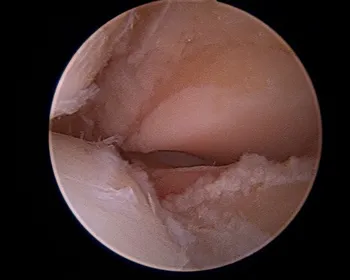

Intraoperative subtalar joint arthroscopy pics

Scarring in the subtalar joint

Scar tissue at the middle facet